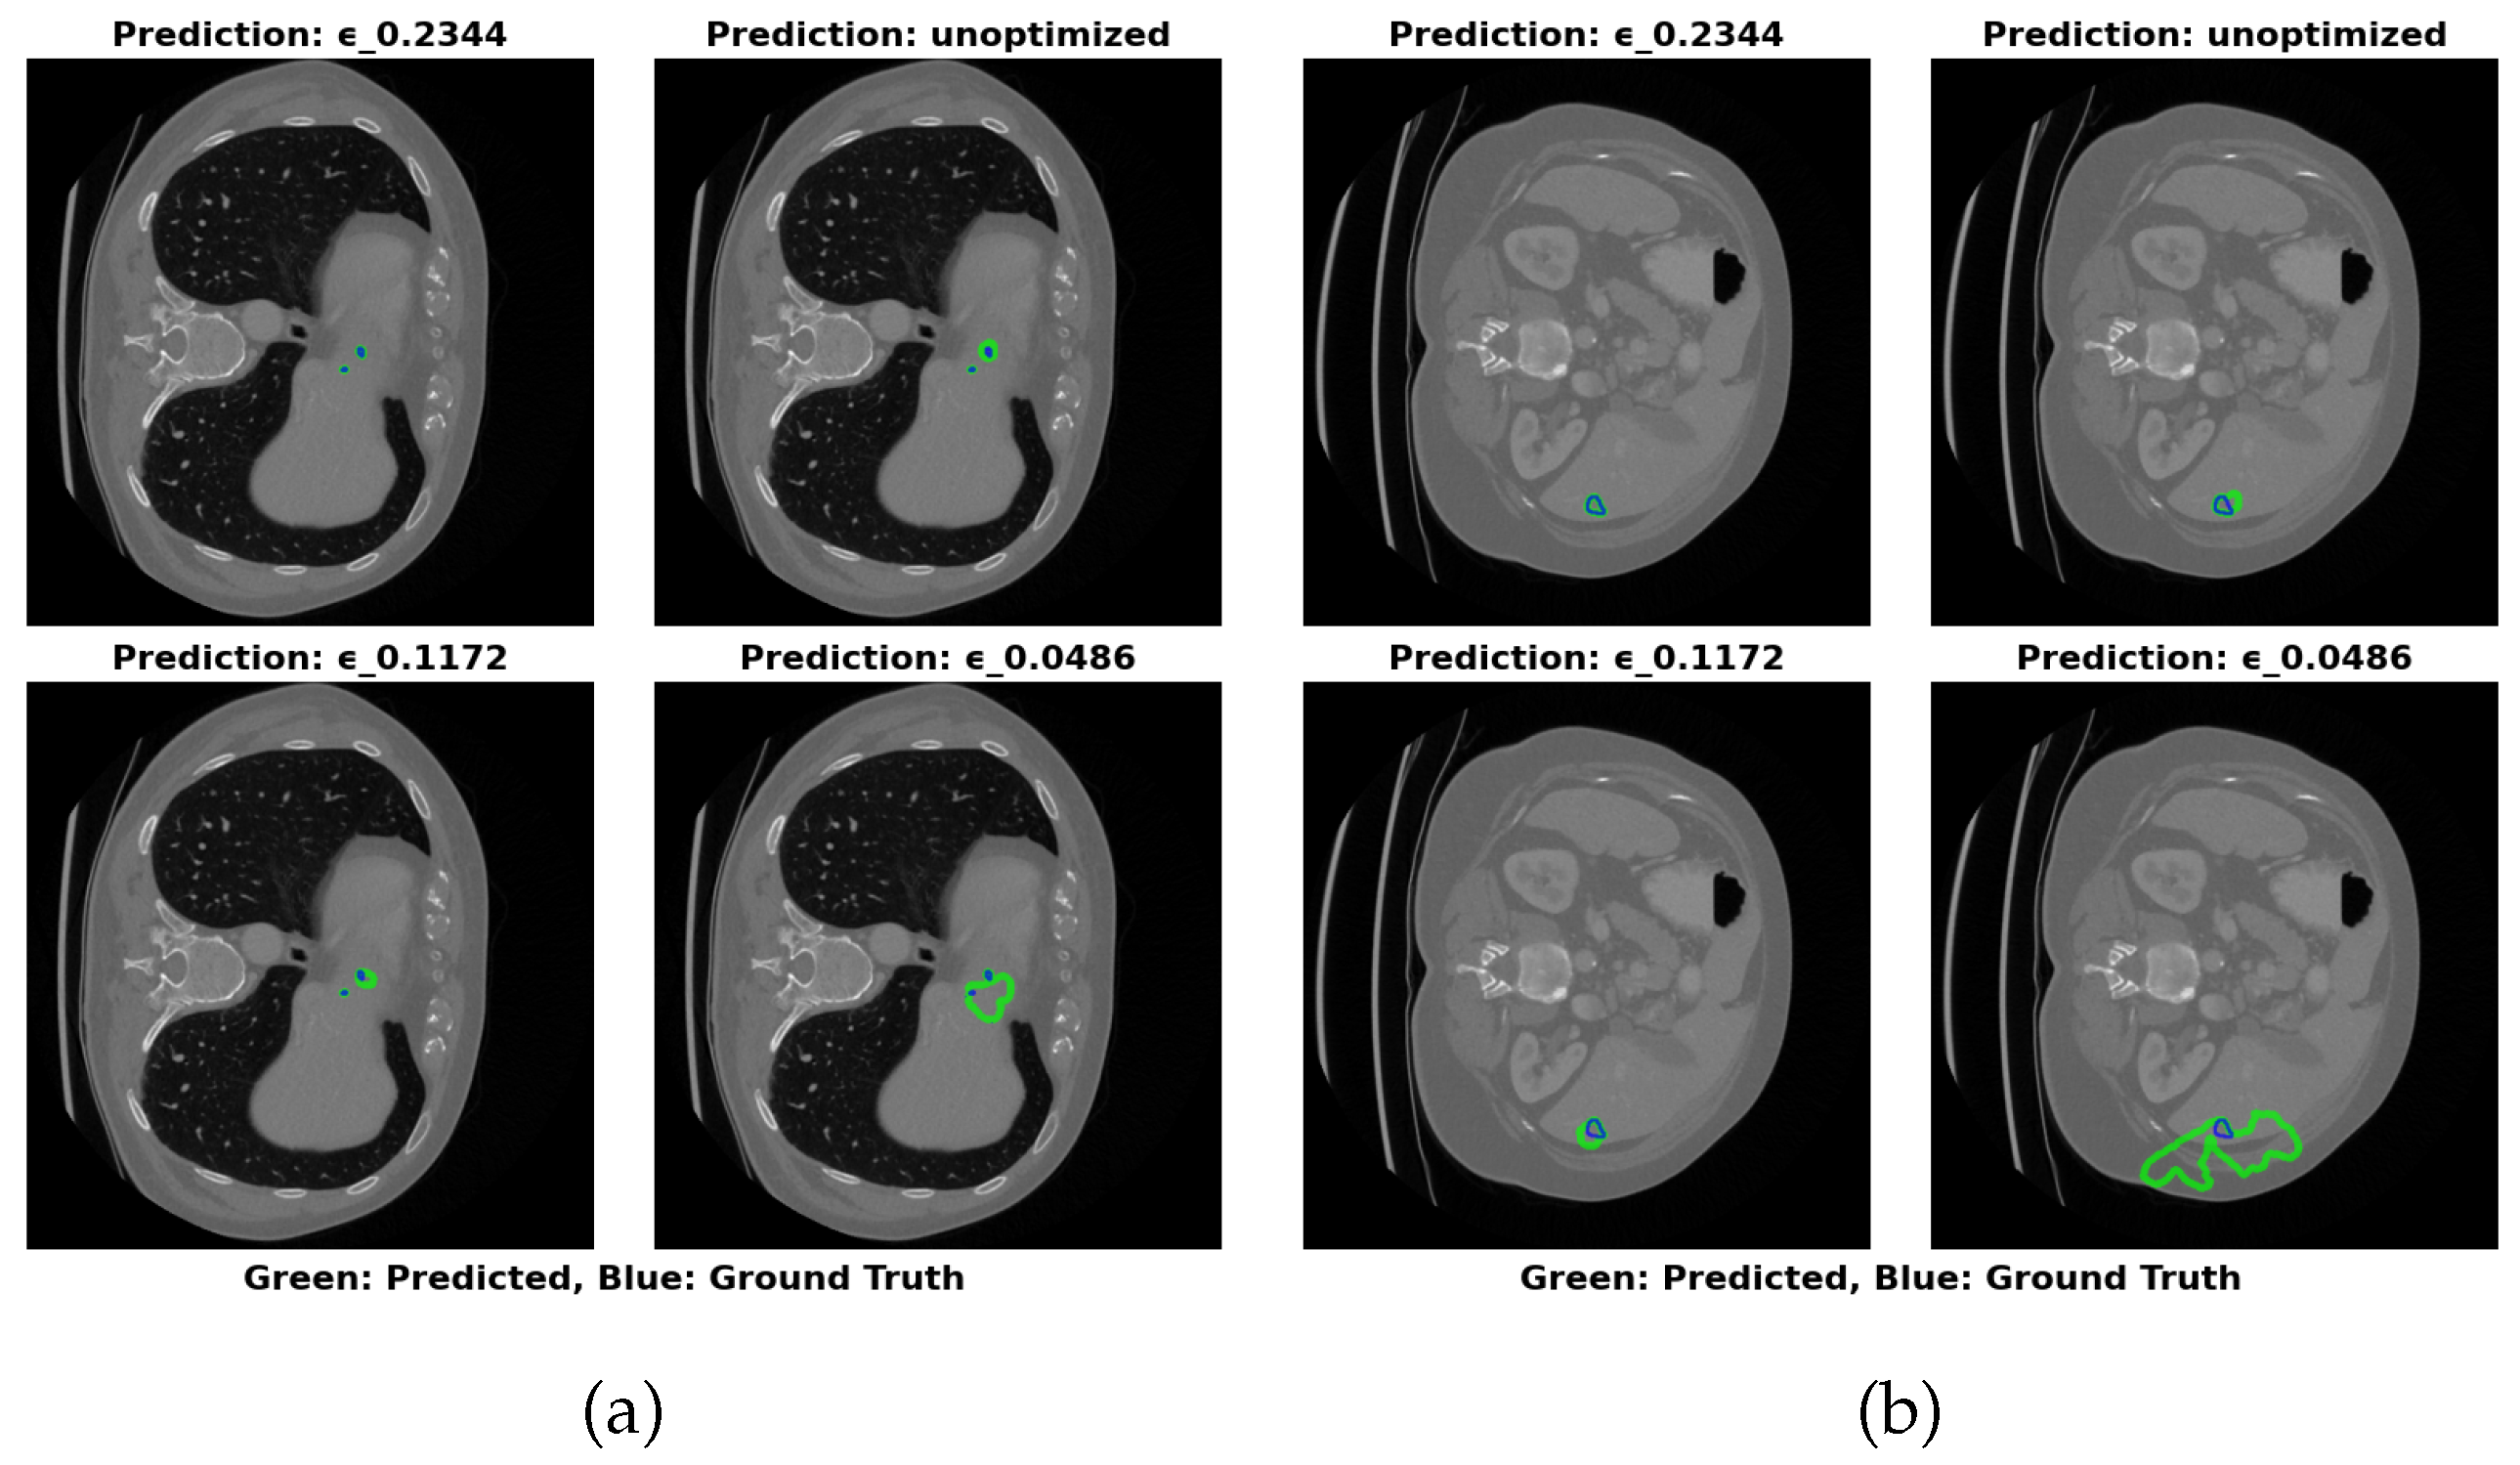

The visual segmentation results presented in Figure 4 support these findings. The configuration with ϵ =0.2344 exhibits the most accurate tumor boundary predictions, with minimal deviation from the true boundaries. In contrast, the unoptimized model, though effective, demonstrates less precise boundary delineation, particularly in complex tumor regions. These visual results confirm the quantitative findings, reinforcing that optimizing ϵ significantly enhances segmentation accuracy and computational efficiency.

Figure 4. Visual Results of Segmentation with Different ϵ Values on IRCADe 3D Dataset

Preprints 152082 g004